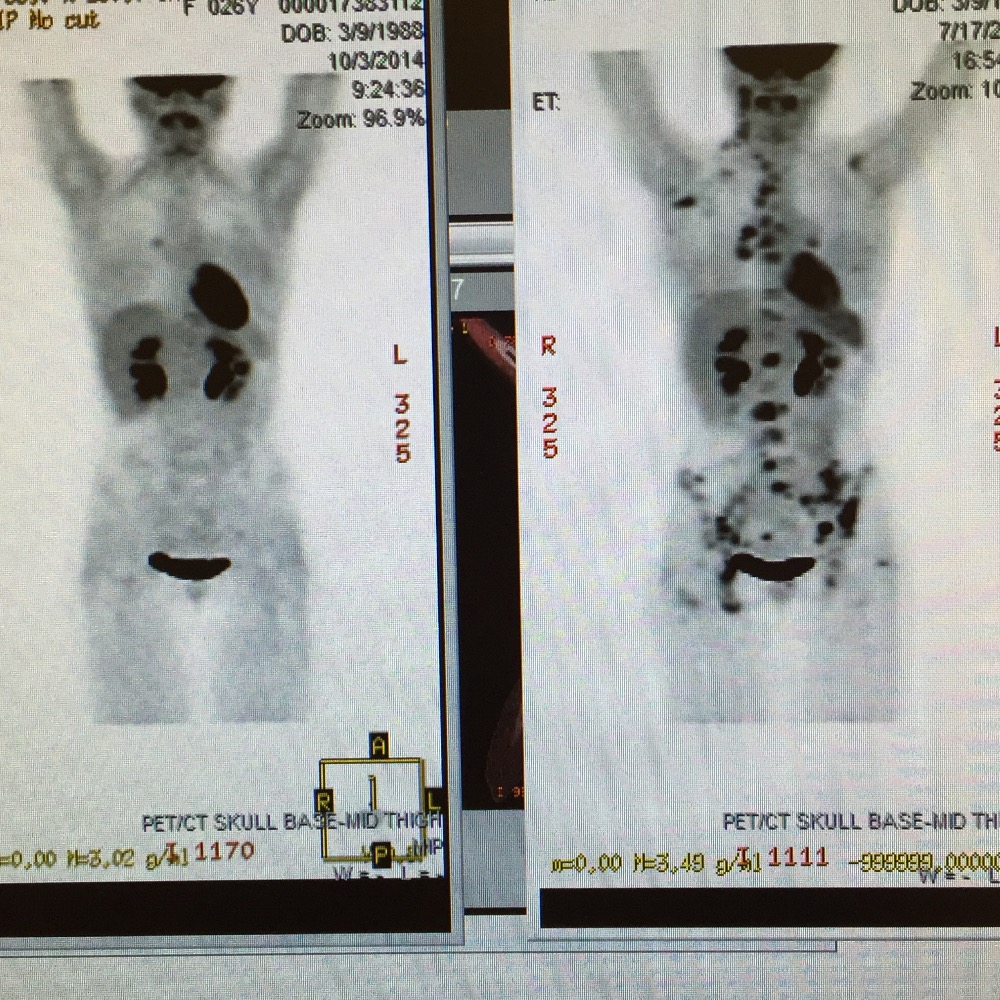

Hi my name is Natasha im 27 years old and I recently married the love of my life. We have been together for 10 years and I couldn't be happier that Kyle chose to love me all this time! He is the the most loving thoughtful man. I am so thankful God brought him into my life. For the past 9 years of our relationship I have been battling Hodgkins lymphona (cancer) I was diagnosed when I was 19 and have been fighting this battle ever since. I have relapsed more times than i can even rememebr at this point. And I have also gone through treatment so many times that i am losing count. There where so many times when we thought we beat this nasty disease only to find out it was back. But still he stuck by my side.

After many long years of fighting the cancer is back yet again. But this time is different than all the rest. The cancer has spread through out my entire body. Including my bones, spine and some organs. Causing an immense amount of pain and fear. The cancer has progressed so much that the doctors have diagnosed me as terminal and haven't given me many more months to live. We aren't sure how much time i have left on this precious earth so we are trying our best to cherrish every moment we have. At this point in my battle with cancer we have exhausted all the treatments for my type of cancer. So we are currently seeking help from a doctor at the City of Hope to find some way to help us. Time is of the essence and we are very scared. And unfortuntely facing something like this comes with a great amount of stress and the need for help. We are headed towards a lot of insurance issues and medical bills. And I have had to unfortuntely quit working (which totally stinks because i love my job it brought so much encouragment to my life but phsyically i just couldn't do it anymore) and not being able to work has taken a huge toll on us financially and we are struggling.